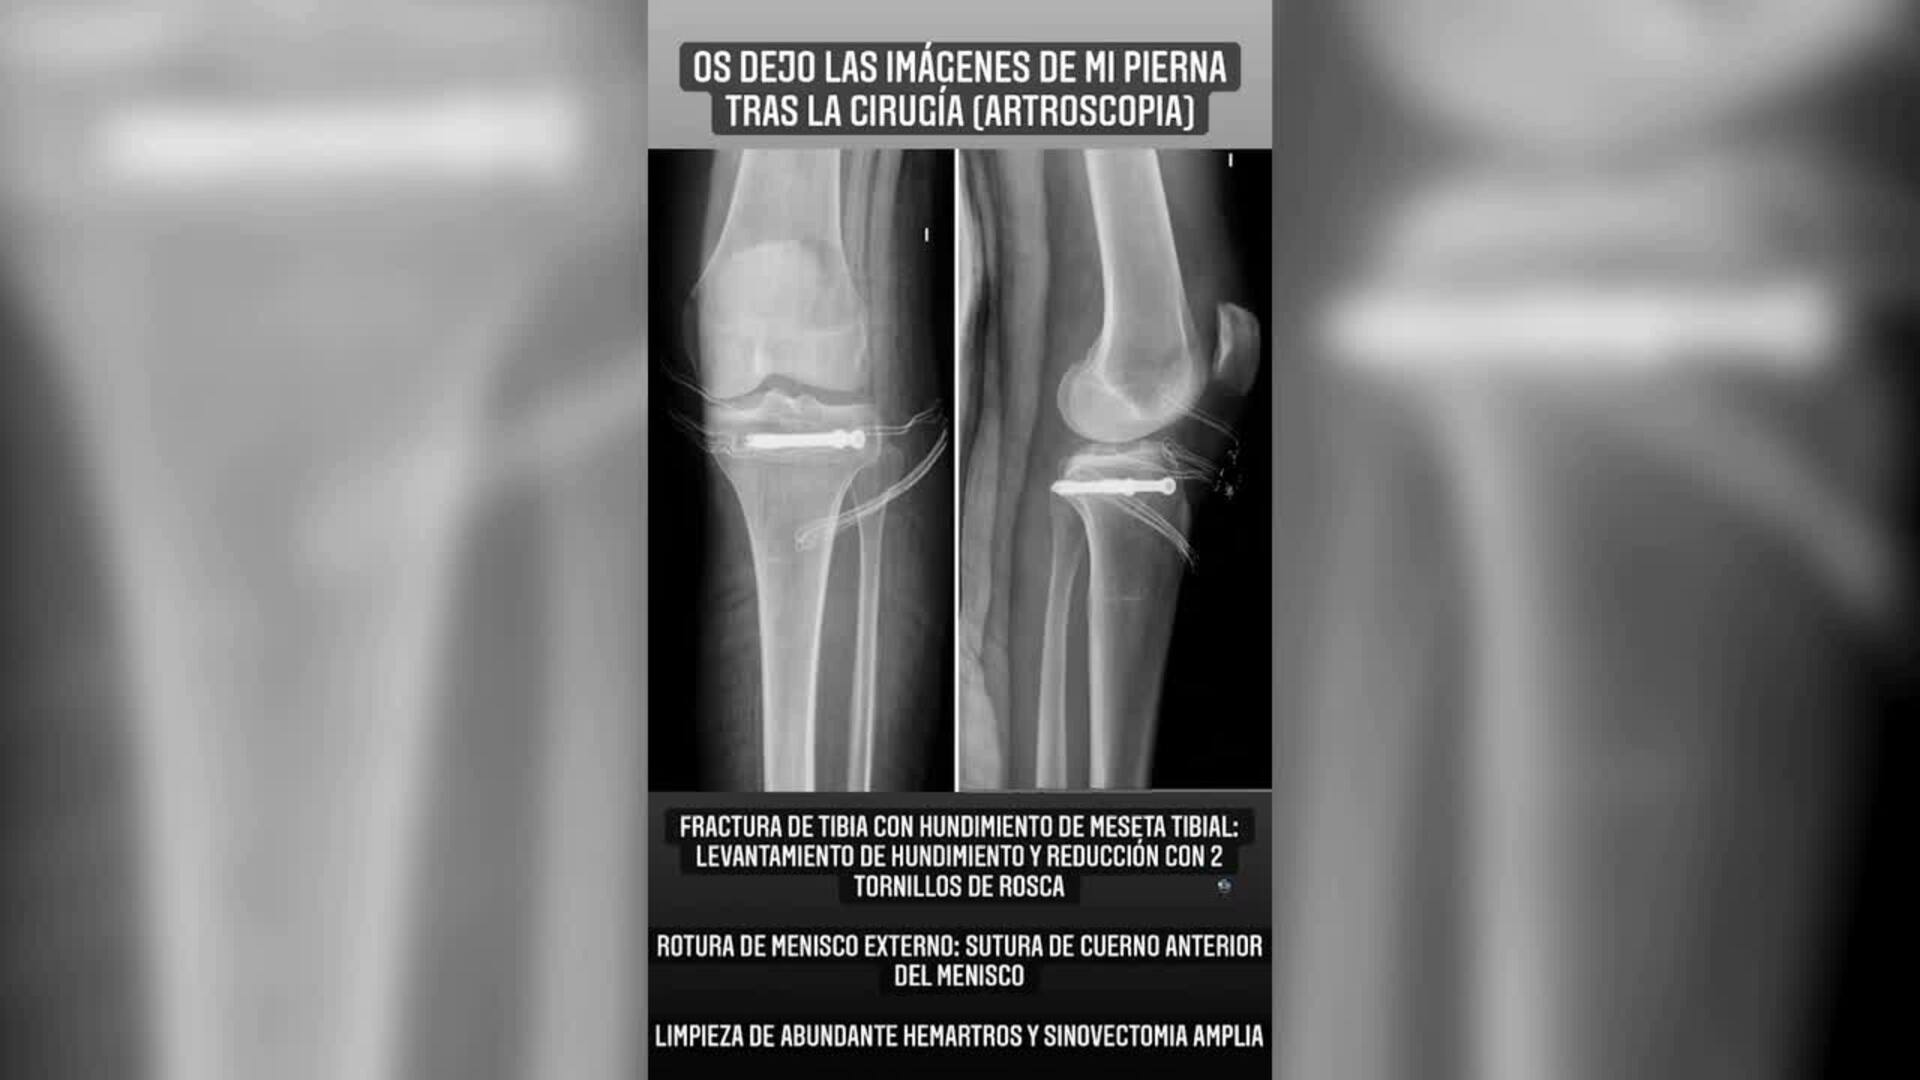

Carla Barber comparte imágenes de su operación tras fracturarse la tibia

Son momentos complicados para Carla Barber, y es que la doctora no parece mejorar en lo que a la recuperación de su tibia se refiere, después de fracturársela esquiando en Baqueira. Este domingo se ha levantado con mucho más dolor, por lo que ha decidido ... moverse aún menos y hacer mucho más reposo para empezar pronto la rehabilitación.(Fuente: Europa Press/Instagram)